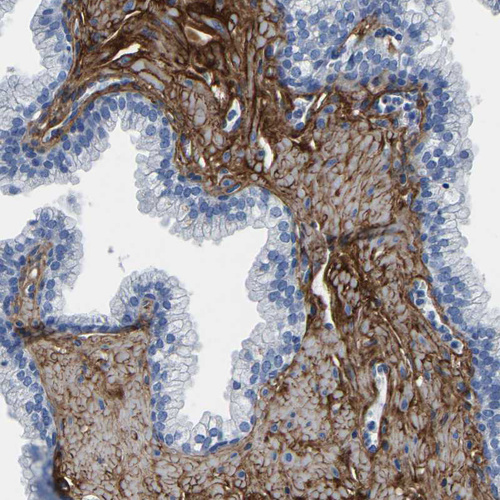

Immunohistochemistry analysis in human prostate and tonsil tissues using HPA019142 antibody. Corresponding COL6A1 RNA-seq data are presented for the same tissues.